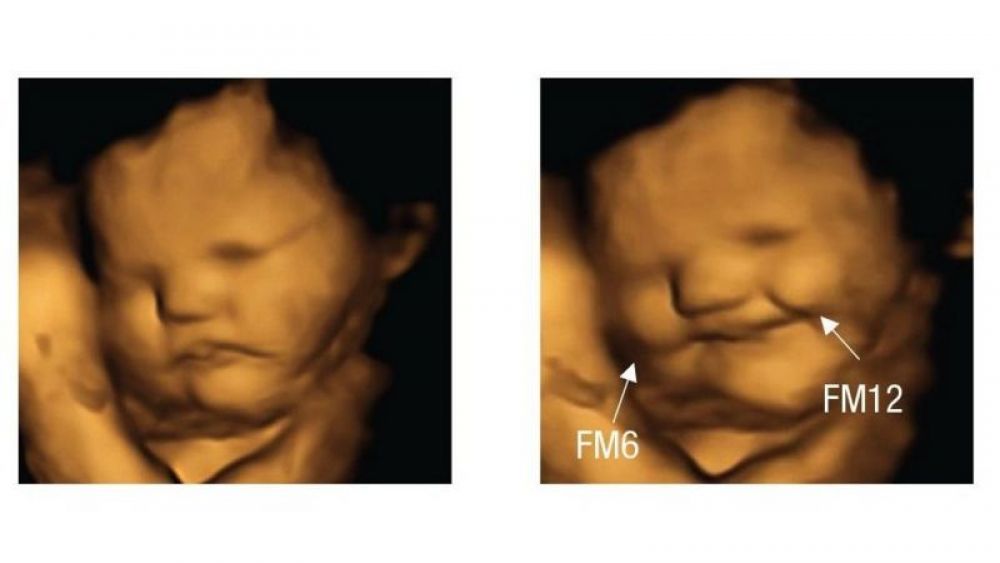

हालै मात्र वैज्ञानिकहरूले गर्भमा रहेको भ्रूण आमाले गाजर खाँदा प्रसन्न हुने र केलको साग खाँदा ठुस्स पर्ने कुरा पत्ता लगाएका छन्।

यूकेको डरम यूनिभर्सिटीस्थित द नियोनेटल रिसर्च ल्याबले भ्रूणले विभिन्न स्वादमा प्रतिक्रिया व्यक्त गरेको प्रत्यक्ष प्रमाण पहिलो पटक अभिलेखीकरण गरिएको जनाएको छ।

साइकोलजिकल साइन्स जर्नलमा प्रकाशित विवरणमा आमाले गाँजर खाँदा गर्भमा रहेको भ्रूण प्रशन्न भएको र आमाले केलको साग खाँदा ठुस्स परेको उल्लेख छ ।

एक सय जना गर्भवतीमा गरिएको परीक्षणमा आमाले खानेकुरा खाएको २० मिनेटपछि भ्रूणको प्रतिक्रिया देखिएको छ । केही नखाएका आमाको गर्भमा रहेका भ्रूणले भने प्रतिक्रिया नजनाएका रिपोर्टमा उल्लेख छ । आमाले खाएका खानाका कारण गर्भमा भ्रूणहरु वरिपरि हुने तरल पदार्थमा विभिन्न स्वाद हुने भएकाले त्यसो हुनसक्ने विज्ञहरुले बताएका छन् ।

आमाले खाने खानाबाट भ्रूणले कस्तो पोषण पाउँछ र बच्चाको स्वास्थ्य विकासका लागि यो निकै आवश्यक छ भन्ने कुरा यसअघिका अनुसन्धानहरूबाट थाहा पाएको भए पनि स्वाद लिने कुरा पहिलोपटक थाहा भएको अनुसन्धान टोलीकी प्रमुख नादिया राइस्लान्डलाई उद्धृत गर्दै बीबीसीले जनाएको छ ।

शिशुहरुले सामान्यतया १४ हप्तापछि स्वाद थाहा पाउने उहाँले बताउनुभयो । यो अध्ययन जन्मने बच्चामा खानेकुराको बानी पार्नको लागि महत्त्वपूर्ण हुने वैज्ञानिकहरुको भनाइ छ ।